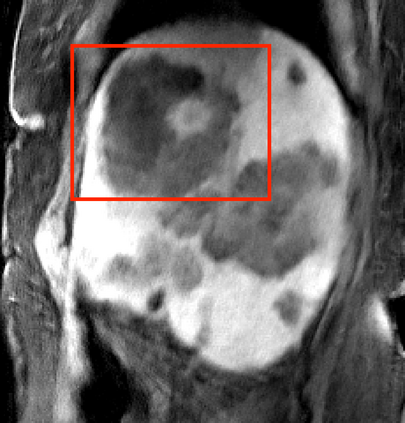

Deep neural networks for medical image reconstruction are traditionally trained using high-quality ground-truth images as training targets. Recent work onNoise2Noise (N2N) has shown the potential of using multiple noisy measurements of the same object as an alternative to having a ground truth. However, existing N2N-based methods cannot exploit information from various motion states, limiting their ability to learn on moving objects. This paper addresses this issue by proposing a novel motion-compensated deep image reconstruction (MoDIR) method that can use information from several unregistered and noisy measurements for training. MoDIR deals with object motion by including a deep registration module jointly trained with the deep reconstruction network without any ground-truth supervision. We validate MoDIR on both simulated and experimentally collected magnetic resonance imaging (MRI) data and show that it significantly improves imaging quality.

翻译:用于医学图像重建的深神经网络传统上是用高质量的地面真实图像作为培训目标来培训的。最近关于噪音2噪声(N2N)的工作表明,有可能使用同一物体的多重噪音测量来替代地面真相;然而,现有的N2N方法不能利用来自各种运动状态的信息,限制了它们了解移动物体的能力。本文件通过提出一个新的运动补偿深度图像重建(MoDIR)方法来解决这一问题,该方法可以使用来自若干未登记和吵闹的测量数据的信息进行培训。MDIR处理物体运动问题的方式是,在没有地面真相监督的情况下,与深层重建网络共同培训一个深层登记模块。我们在模拟和实验收集的磁共振成像(MRI)数据上验证了MDIR,并表明它大大提高了成像质量。